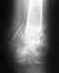

Открытый многоосколчатый перелом обеих костей голени со смещением

Попал в мотоаварию в сентябре,пролежал 10 дней на вытяжке,и 19 установили аппарат иллизарова,после чего сделали несколько корректировок

и получился вот такой результат,скажите,все ли стоит как положено?или имеет смысл обратиться в ЦИТО?С конечным результатом хожу уже с 15 октября,снимок сделали 8 ноября,и вот выкладываю